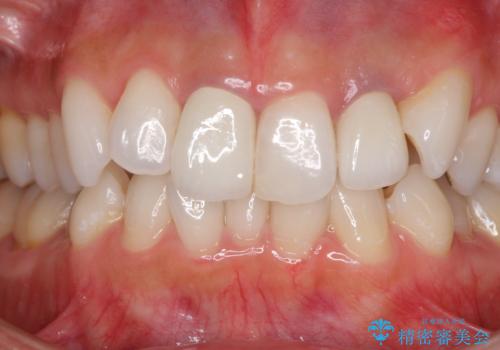

むし歯は歯肉内にまで進行していると外科処置が必要となりますが、ギリギリの位置でとどまっていたため、速やかにオールセラミッククラウンにて補綴治療することとしました。

むし歯は多かったものの、歯肉の腫脹はそれほどなかったため、最小限の治療回数で治療を終えることができました。